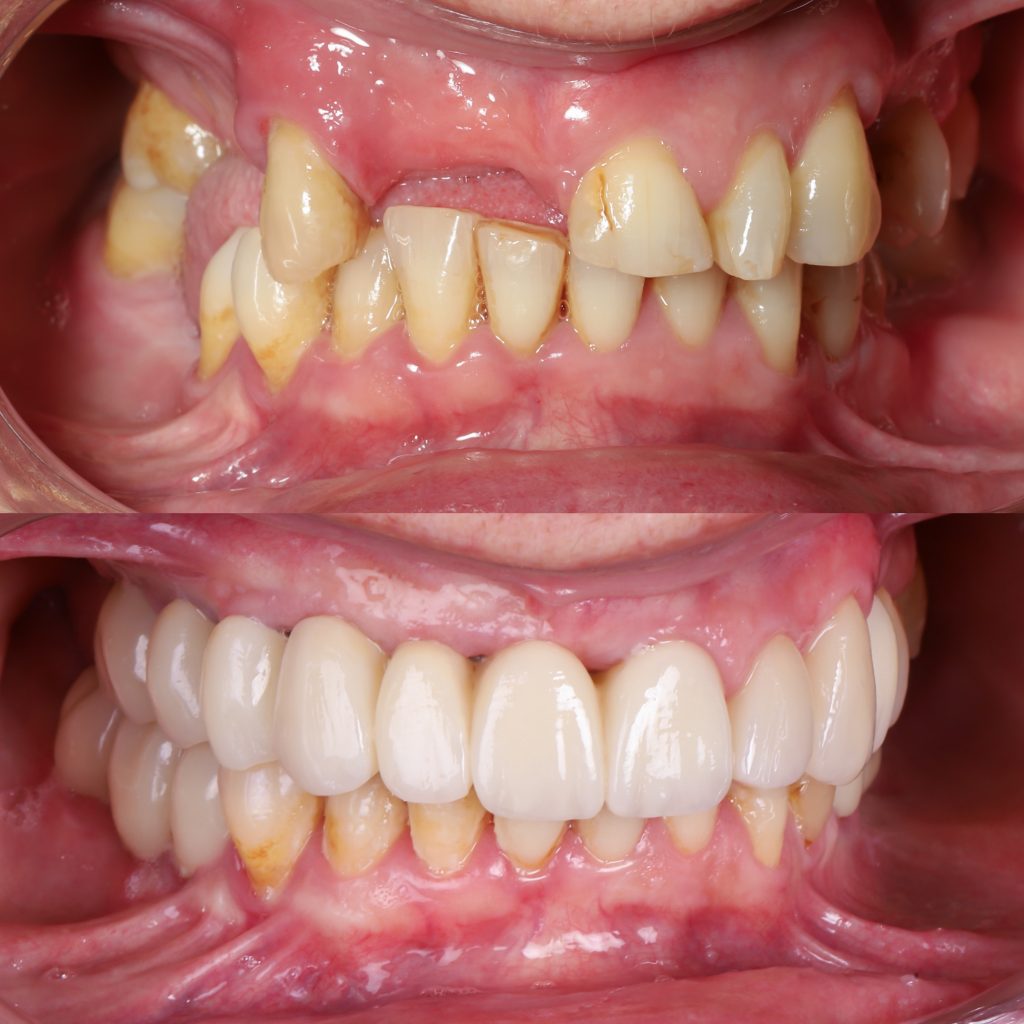

Historias de transformación

Si alguna vez te han dicho que tu caso no tiene solución, en Alejandro Prieto Dental desafiamos los límites de la odontología para ofrecerte la respuesta que estabas buscando.

Before

After

Visualizar la transformación

Los cambios de imagen de la sonrisa favorecen mejoras cuidadosas y matizadas, para obtener resultados naturales que garanticen el equilibrio general y la armonía facial.